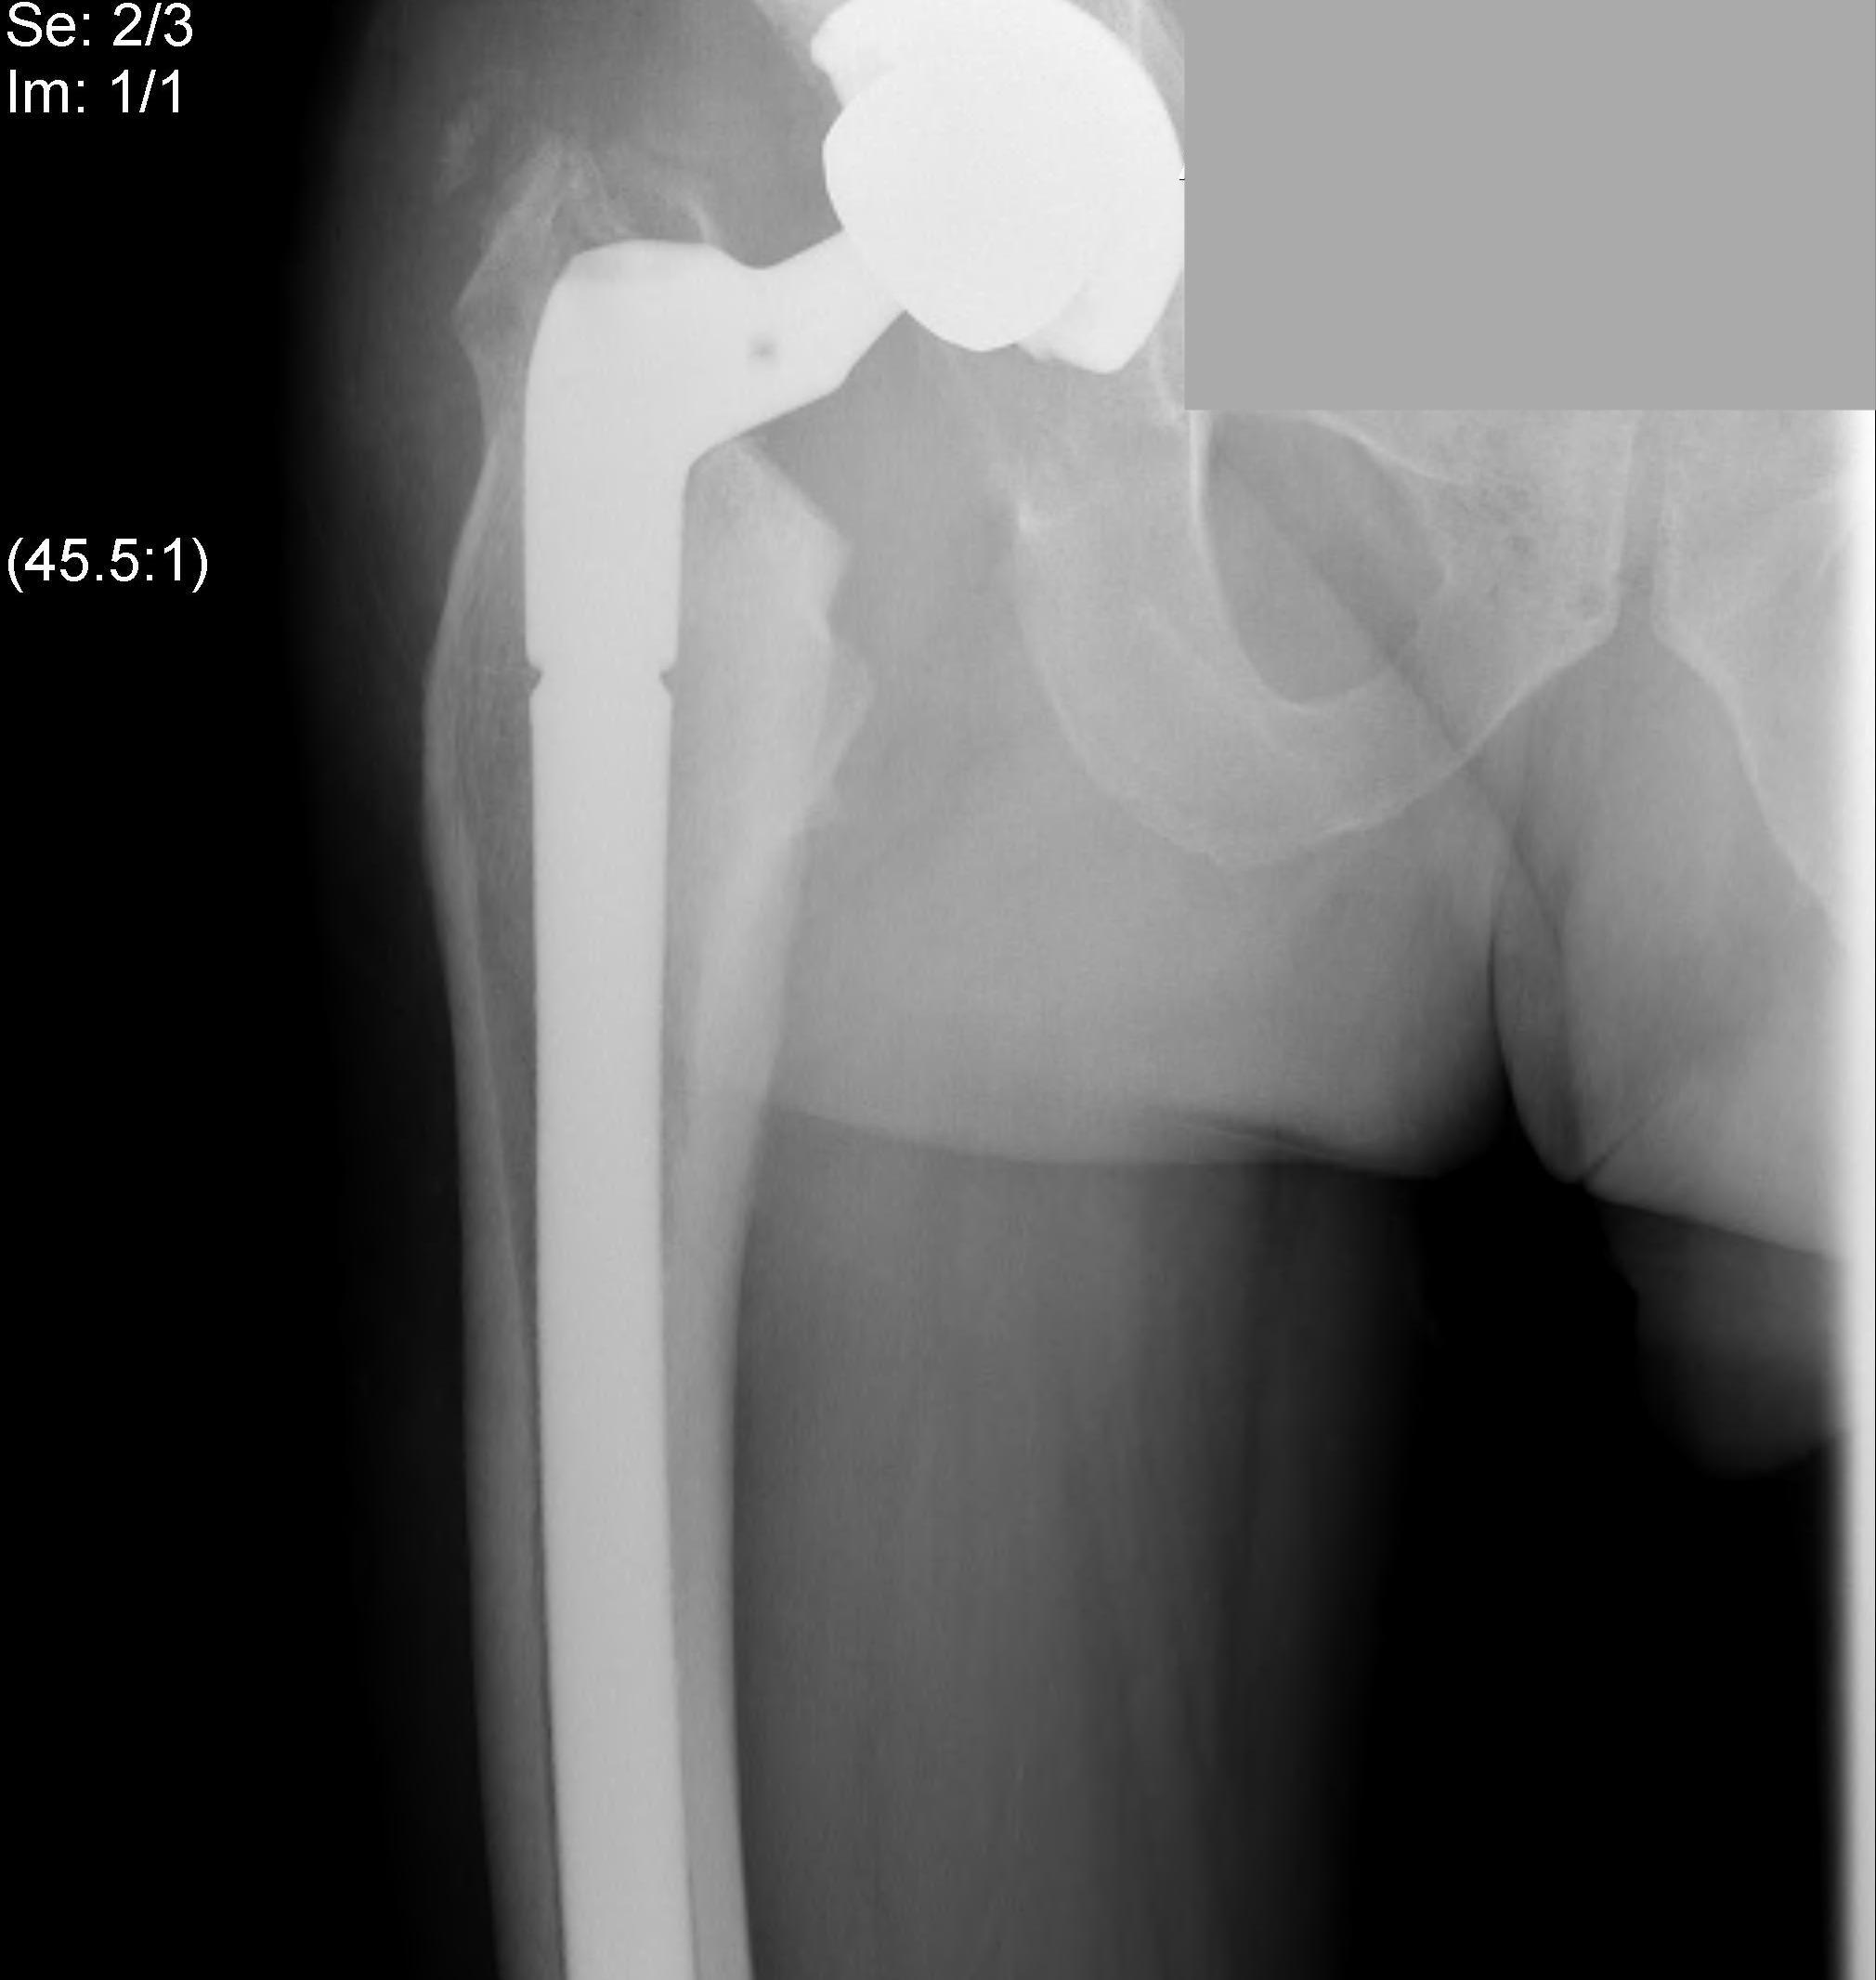

Uncemented stem

Modular stem

Trochanteric slide

Results

Hanna et al Arch Orthop Trauma Surg 2017

- 6 studies and 245 THA in Perthes

- intra-operative fracture 11% reduced with used of modular stems

- sciatic nerve palsy 3% associated LLD 1.9 cm and previous surgery

- 99 THA for Perthes

- follow up 8 +/- 5 years

- 10% revision rate

- 9% intraoperative fracture (mostly femur)

- 3 sciatic nerve injury with lengthening of 2.2 +/- 1 cm